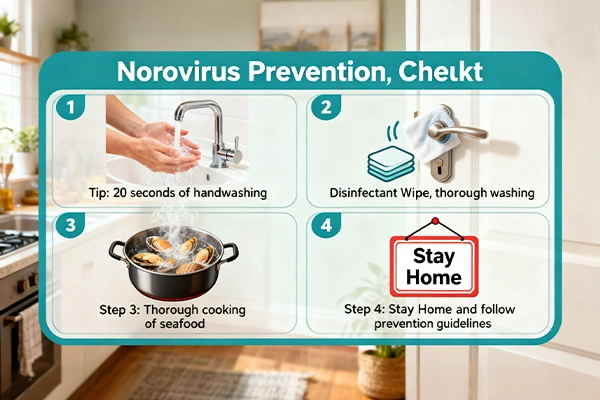

Since there is no vaccine for norovirus, prevention relies on stopping transmission. Key strategies include:

- Handwashing: Use antiseptic soap and water for at least 20 seconds (hand sanitizers with <60% alcohol are less effective against norovirus).

- Surface Sanitization: Clean and disinfect surfaces (e.g., countertops, toilets, phones) with bleach-based cleaners to kill the virus.

- Safe Food/Water: Cook shellfish thoroughly, wash produce with clean water, and avoid drinking untreated water.

- Avoid Close Contact: Stay away from infected people, and keep sick individuals home from work/school.